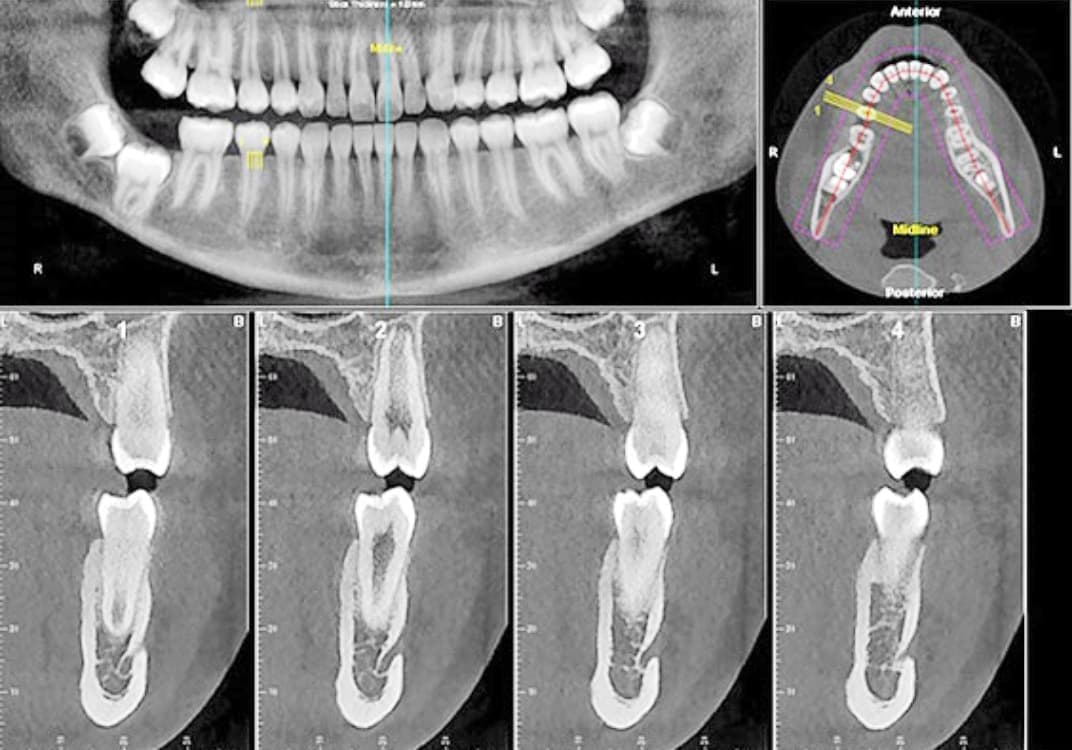

CT 3D デジタルレントゲン

HCT 3D Roentgen

高精細で被爆量も少なく安心

当院では、歯科用CT3Dデジタルレントゲンを活用し、身体への負担を少なく、状況を詳しく把握し、的確な治療を提供出来るよう心掛けております。

CTデジタルレントゲンに使われているX線センサーは高感度で照射時間も短く、より低線量でのレントゲン画像の取得が可能となり、お子様にも安心です。

インプラント手術や歯周病治療、歯列矯正治療、歯の根の病気に関係する治療の正確な診断、治療計画には、3DCTによる撮影が欠かせません。

例えば、親知らずの抜歯や骨内に埋伏している過剰歯の抜歯等、正確な位置や神経や血管等との距離を3次元的に把握することで負担の少ない安心な処置が行えます。